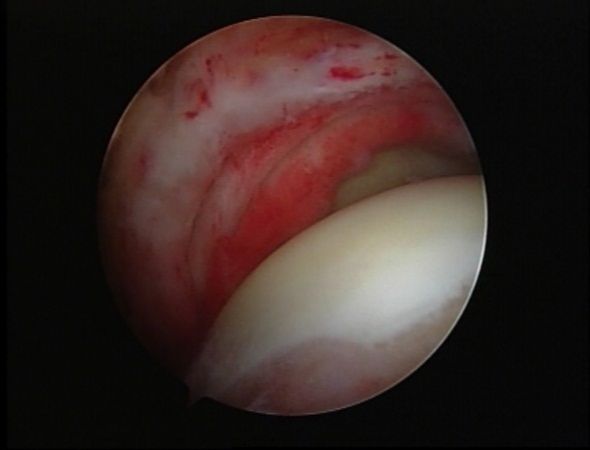

肩袖巨大撕裂镜下缝合修复